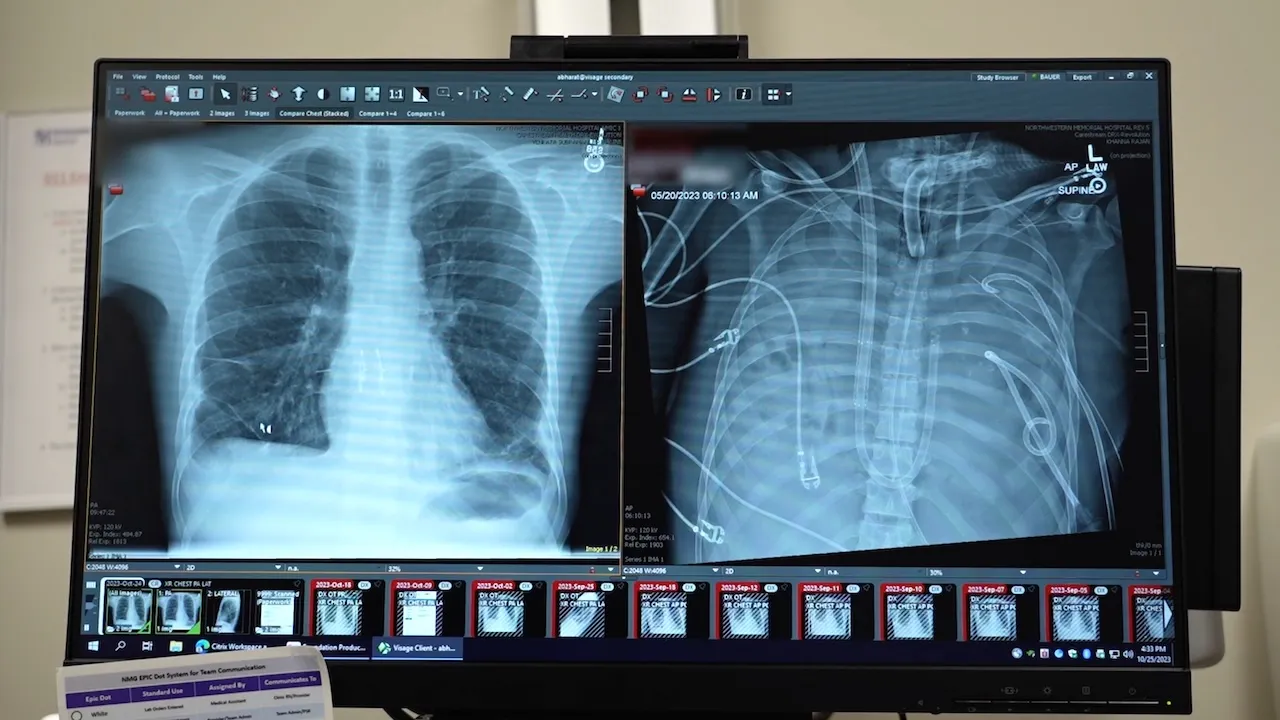

The patient, a 33-year-old from Missouri whose identity remains undisclosed, arrived at Northwestern Memorial Hospital in the spring of 2023 due to lung failure stemming from an influenza-related illness.

Dr. Ankit Bharat, chief of thoracic surgery and executive director of the Canning Thoracic Institute at Northwestern Medicine, explained, “He had developed a lung infection that was resistant to all antibiotics, resulting in liquefaction of the lungs and the infection spreading to other areas of the body.” This necessitated the removal of his lungs to prevent further complications, although there was a significant risk of immediate heart failure.

A case study published recently highlighted a “molecular analysis” of the removed lung, revealing extensive scarring. This finding reinforces the argument that, in severe cases of acute respiratory distress syndrome, transplantation can be the only feasible solution.